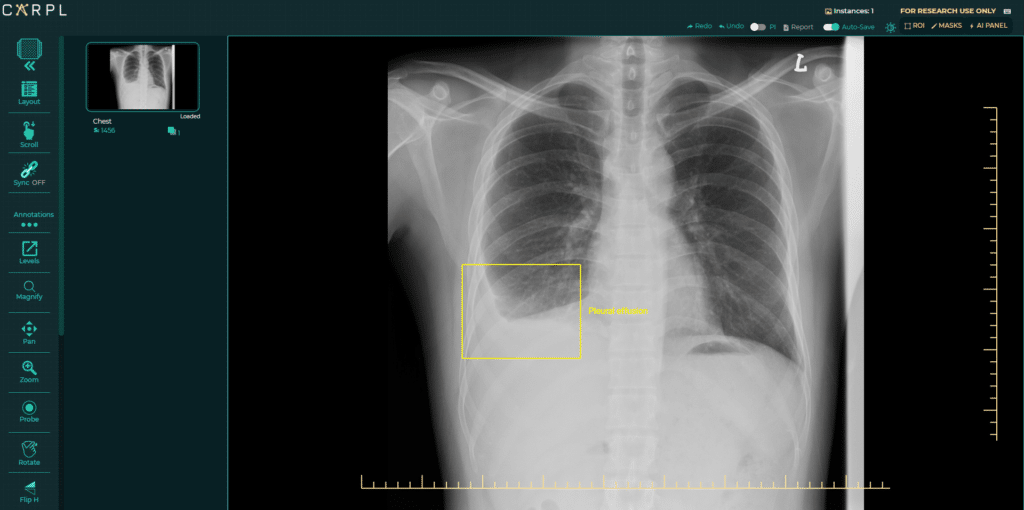

A savoir que, Lunit avait déjà déployé, en novembre 2022, une IA pour l’analyse des radiographies pulmonaires aux États-Unis, en Australie, au Brésil, en Inde et à Singapour via la plateforme CAPRL.